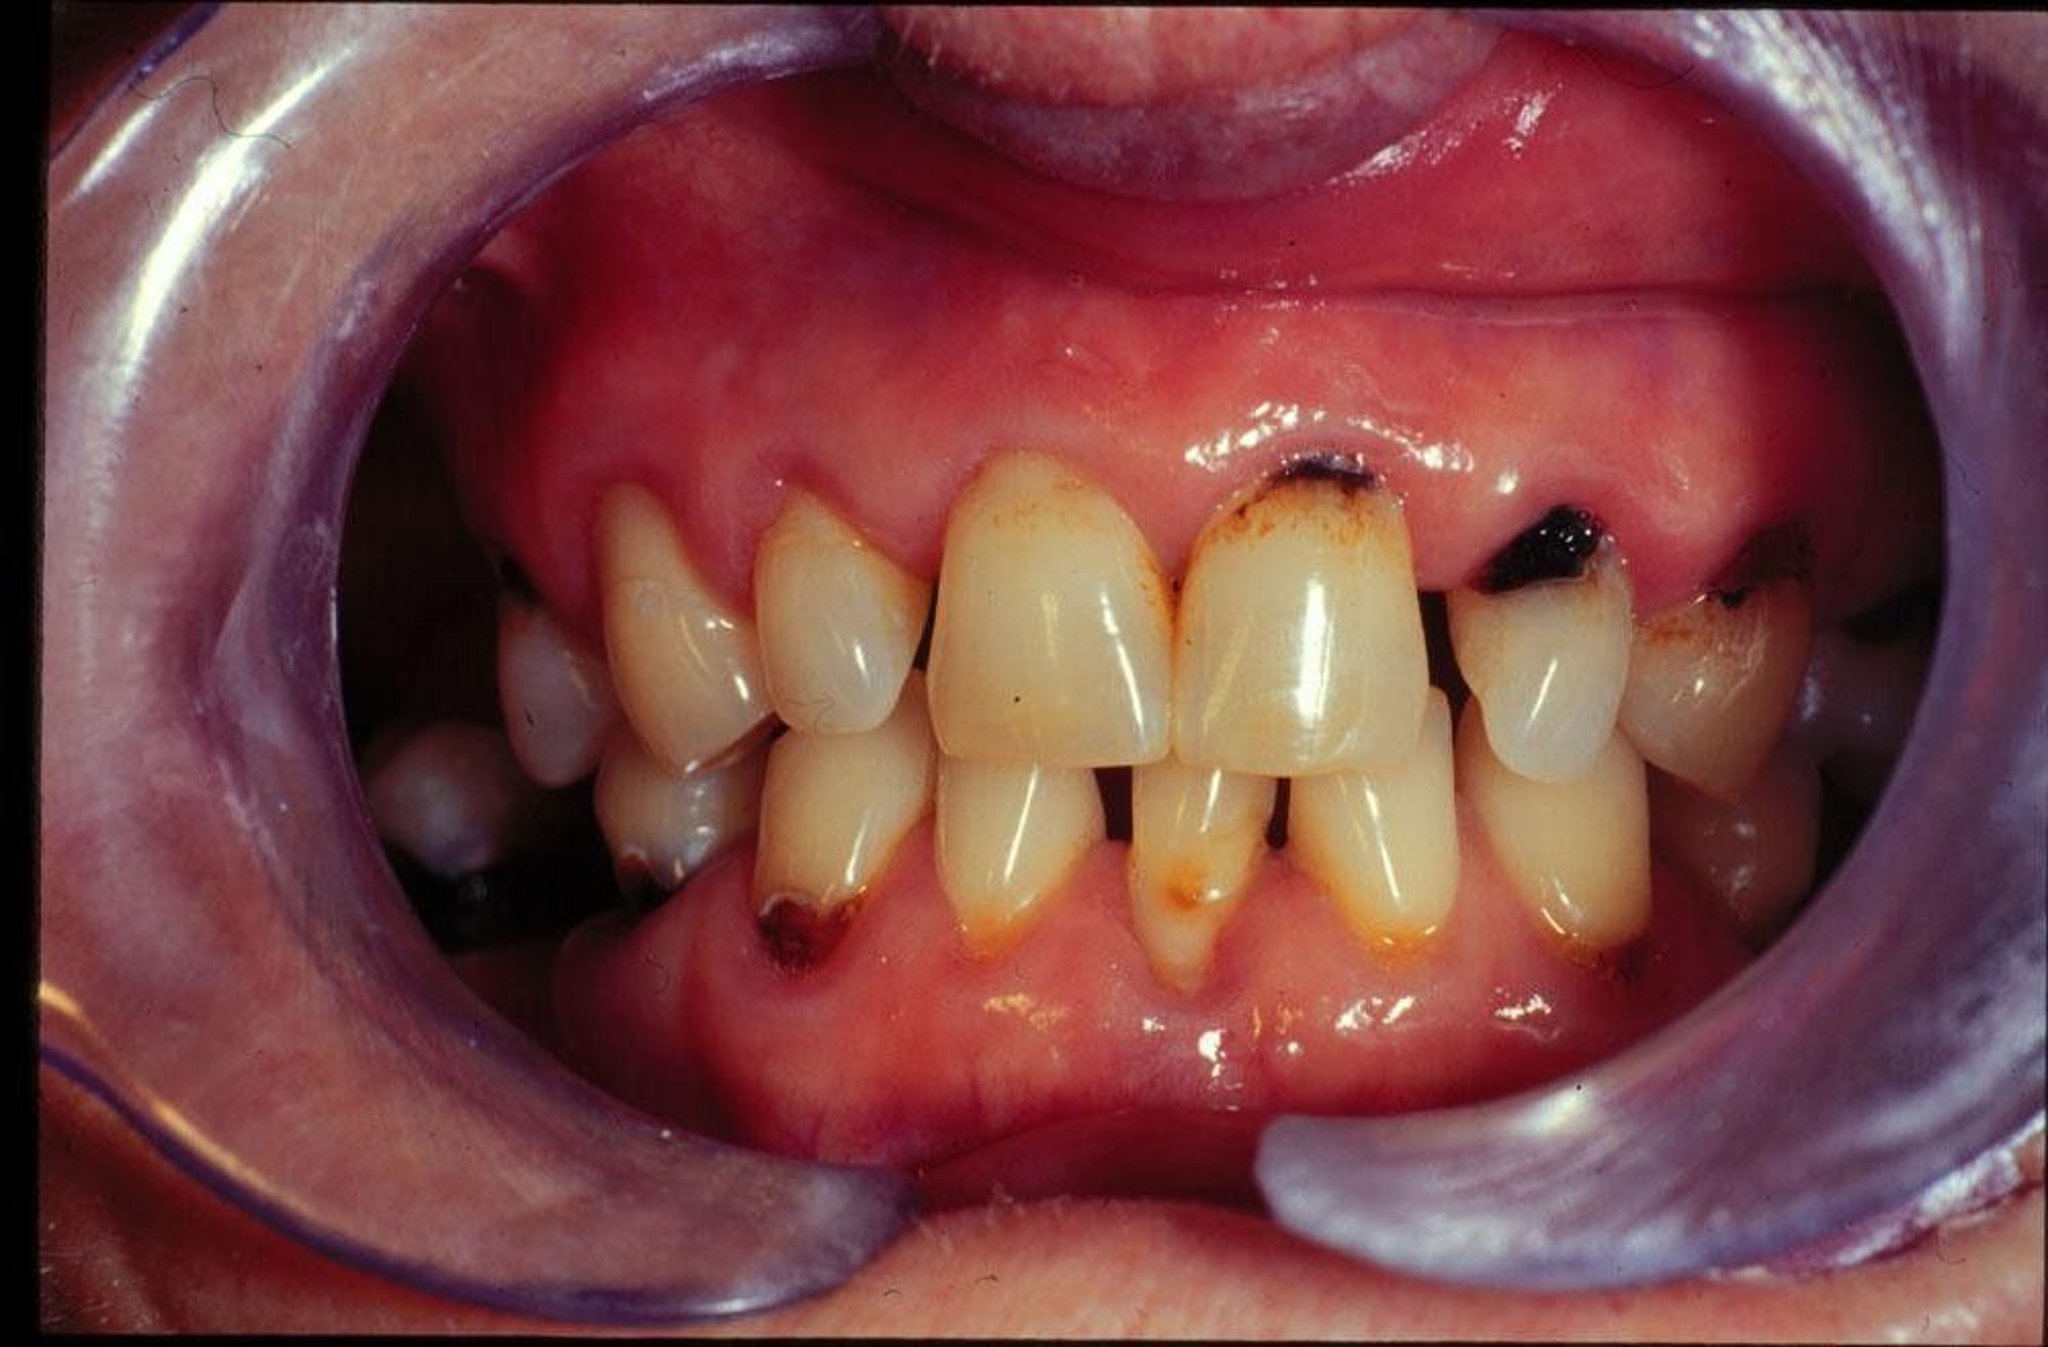

This image shows new and recurring cavities in a person with dry mouth.

Image provided by Jonathan A. Ship, DMD.